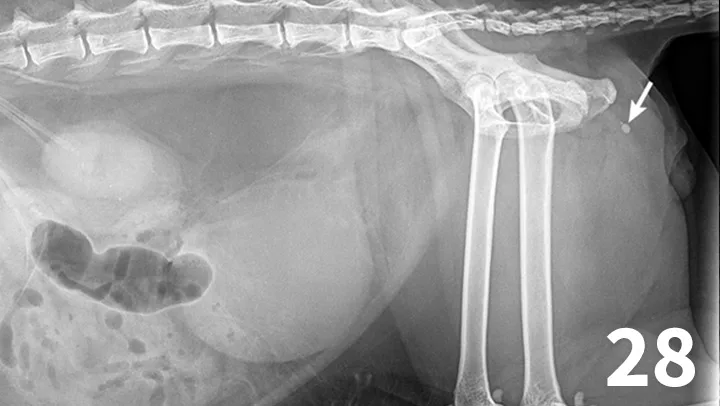

The normal urethra of dogs and cats is difficult to visualize on survey radiography and ultrasonography. Radiopaque urethroliths can be observed on survey radiographs, and therefore the entire urethra should always be included in the field of view (Figure 28). In male dogs, it is useful to pull the hindlimbs forward to assess the urethra between the pelvis and os penis (Figure 29). The prostate gland and proximal urethra, before entering the pelvic canal, can be visualized with ultrasonography, especially if there is urethral distention. In male dogs, the urethra at the proximal os penis can be evaluated with ultrasonography to assess for urethroliths, which commonly lodge in this location. Positive-contrast retrograde urethrography is the best tool for diagnosis of intraluminal, intramural, and extramural compressive urethral disorders as well urethral rupture (Figure 30).

Figure 28.

There are 1 small and 1 large round urethral calculi (arrow) in this cat with urinary obstruction. The bladder is severely distended, and there is decreased detail caudal to the bladder. This demonstrates the importance of including the entire urethra on radiographs when urinary bladder obstruction is present or suspected.